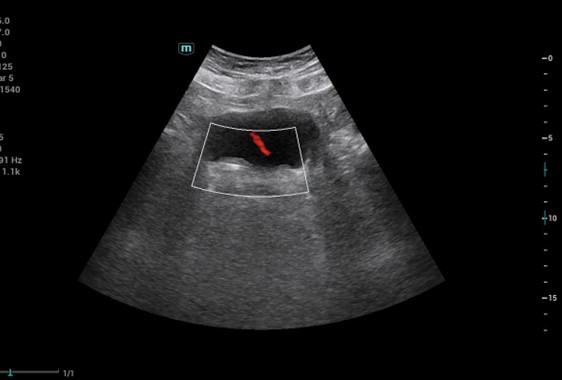

1. Manejo de cólico nefrítico con hidronefrosis grado II en hombre de 63 años y situación familiar compleja que impide manejo hospitalario.